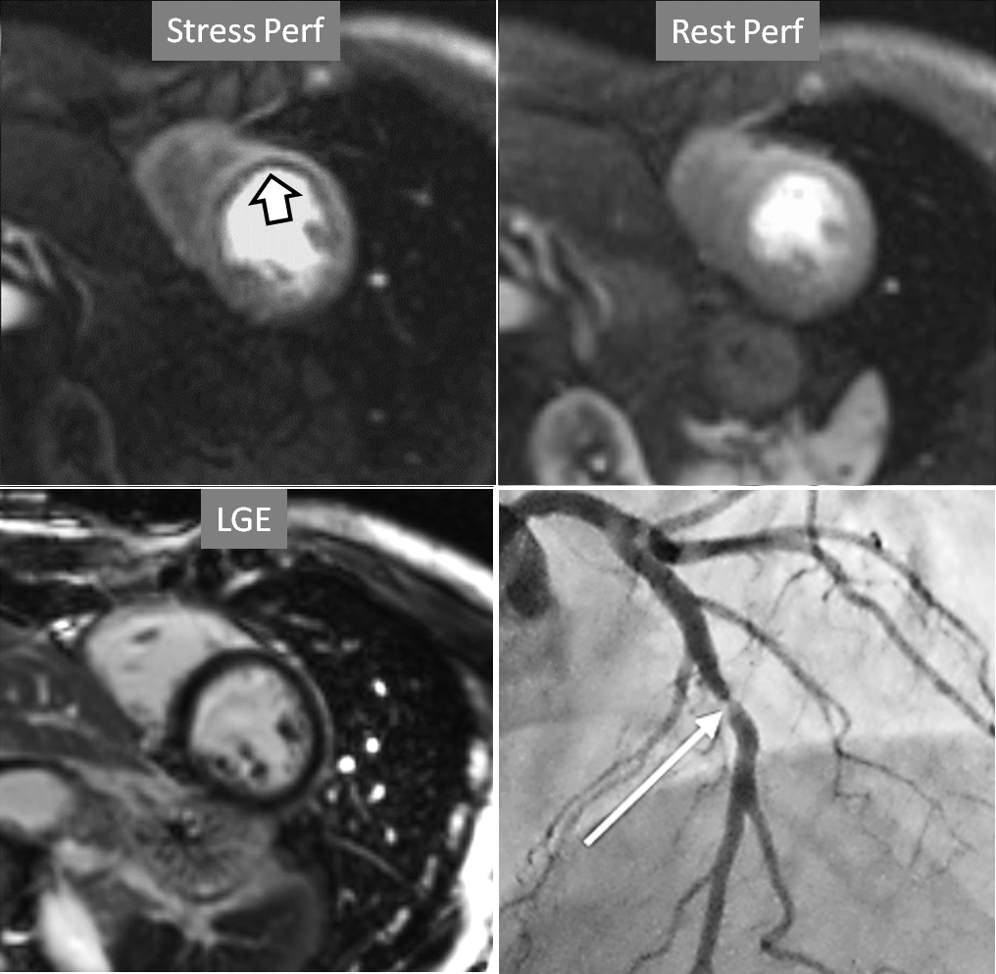

Perfusion defects in different territories can be detected in case of multivessel disease (Fig. 7) and, in patients with severe 3-vessel CAD, the perfusion study may show a global, intense, persistent defect which is readily recognizable (Fig. 8).

Fig. 7.Two-vessel perfusion defect. Stress perfusion defects at the anterior (white arrows) and inferior (black arrows) walls, not present at rest. Angiography (right panels) shows significant stenoses (white arrows) of the LAD (upper panel) and the right coronary artery (RCA) (lower panel).